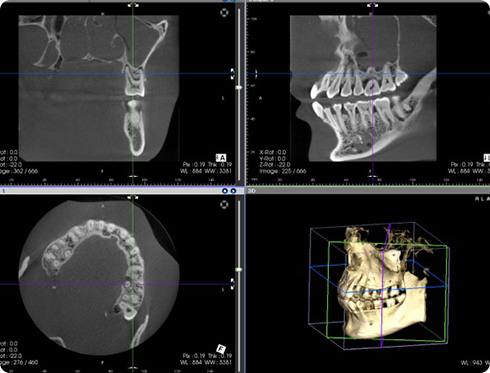

歯というのは1本1本が独立しているのではなく、周りの組織や他の歯とも密接に関係し合っています。カウンセリングの内容をもとに総合的な診断をするためには、症状のある部分だけでなく、お口や顎の状態全体を見る必要があります。お口全体の写真、レントゲンのほか、顕微鏡によるプラークの検査や歯科用CTによる骨の状態の確認など患者さんごとに必要に応じた検査を行います。

資料や検査結果をもとに、現在の状態、それに至った原因、治療方法をCTモニターやiPadを用いて、わかり易く説明させていただきます。計画書や見積もり書などもお作りできます。治療方法は1つではないため希望に添わない場合やわからない場合は何度でもご説明します。